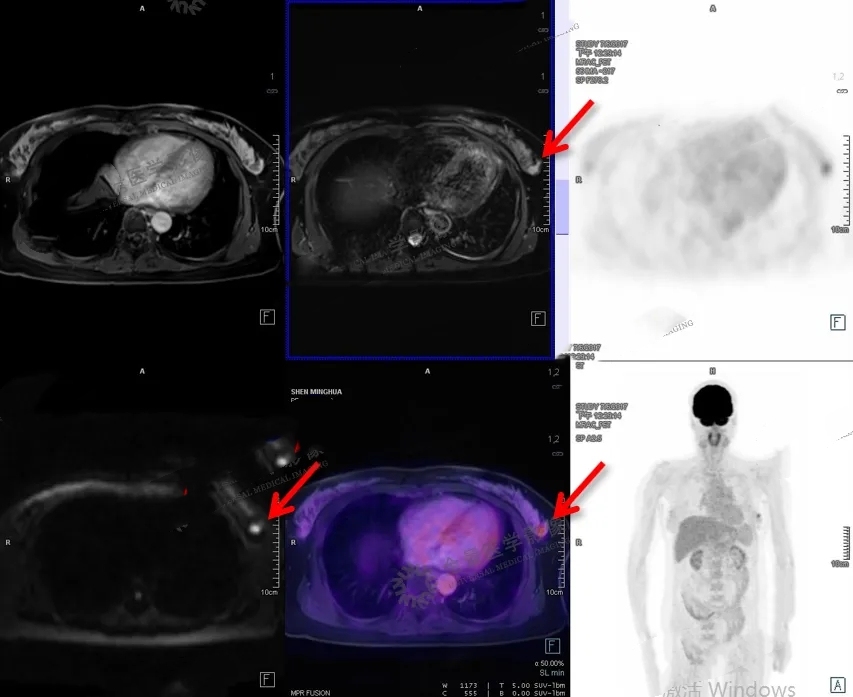

2. 全身PET-MR,可以发现4mm大小超早期原位癌,无辐射;

3. 一次性全身无死角筛查全身超早期肿瘤;